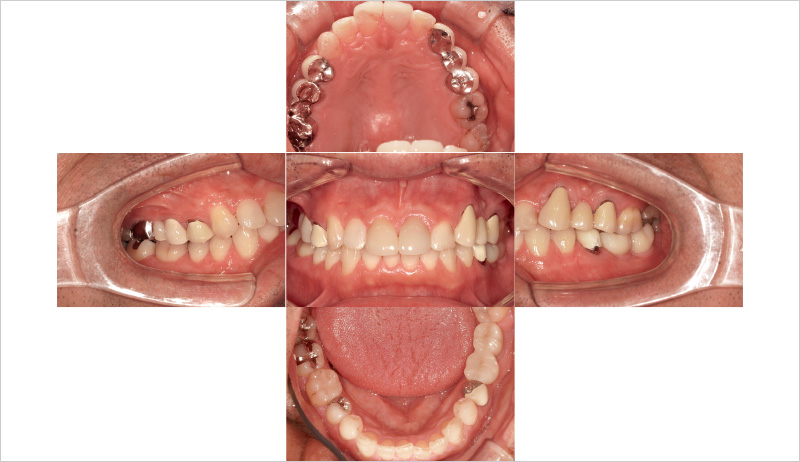

51歳男性、主訴:左下の奥歯で噛めるようになりたい(図14, 15)。

この症例が私にとって初めてのSPIインプラント症例だった。ドリルキットがとても簡便で操作性も良く感じた。こちらの症例は初心者でもできる症例を挙げているので参考にしていただけたらと思う(図16~19)。

まずフラップを開く前にヨード染色を行い、付着歯肉の幅を確認する。その後、フラップを全層弁で開く(私の場合はそこまで大きくは開けないことが多い)。床形成を行い平行指示ピンを入れ平行性を確認。SPIイニセルインプラントをコンディショニングした状態で埋入の準備を行う。₅:φ4.0長さ11mm、 ₆:φ4.5長さ11mmのSPIイニセルインプラント エレメントRCを埋入。付着歯肉を減らさないように縫合を行った。

![[写真] 初診時の口腔内写真](/academic/dentalmagazine/wp-content/uploads/sites/2/2025/09/194-8_photo14.jpg)

図14 初診時の口腔内写真 -